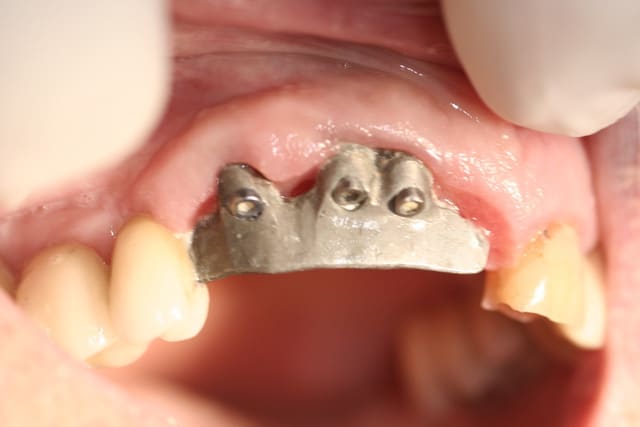

bridge en place depuis plus de 8 ans, assymptomatique, pas de mobilité, à la palpation on les sent sous muqueux

si le patient est content moi je suis content, il ne m'a rien demandé je ne lui ai rien dit

C'est beau de faire des chirurgies flapless !!!

même pas il décollait des lambeaux pour les mettre